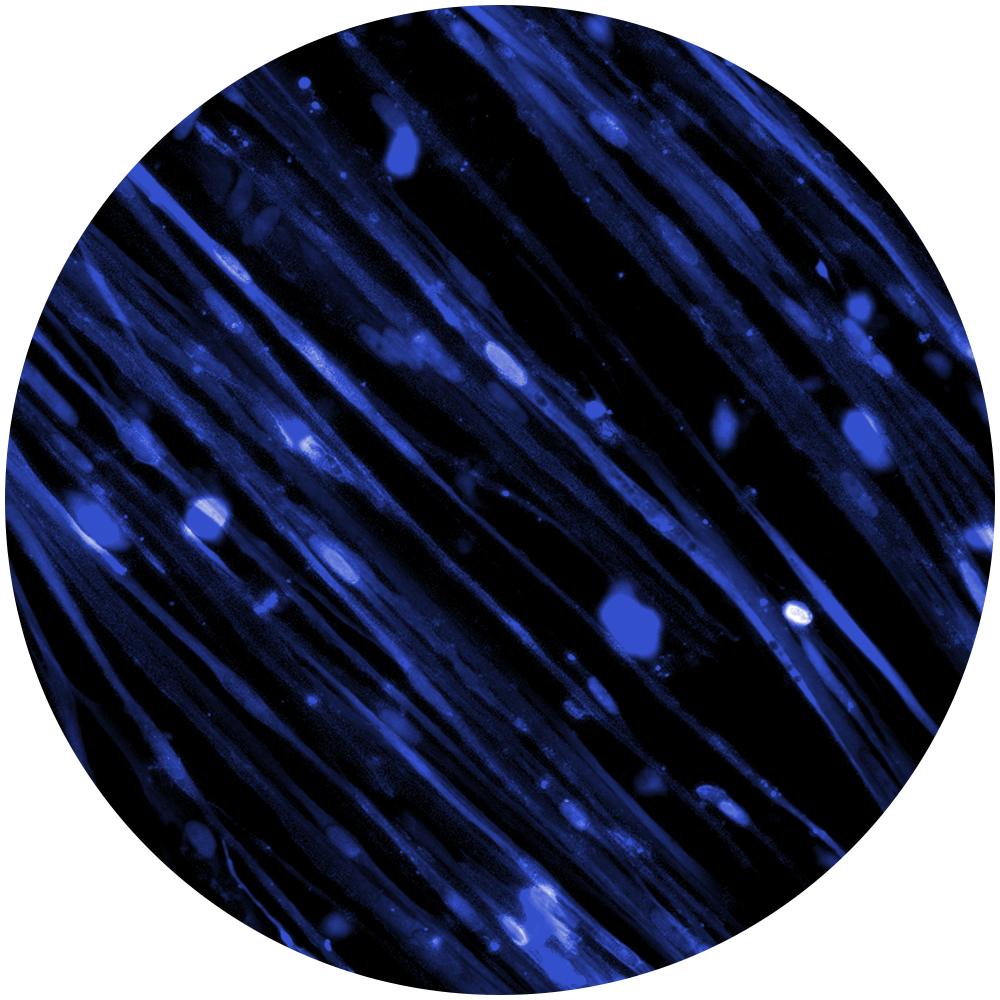

Muscular Dystrophy, Fasciocapulohumeral Muscular Dystrophy

Karin received her doctorate from the University of Oxford, United Kingdom, in the Department of Physiology, Anatomy and Genetics, studying “Spinal Muscular Atrophy, disease mechanisms and therapeutic approaches”. She has an MSc. in Neuroscience and Cognition, and a BSc. in Cognitive and Neurobiological Psychology from the University of Utrecht, The Netherlands. She completed two internships, one at the University of Utrecht, investigating food addiction in rats, and a second, at the University of Oxford, United Kingdom, investigating the role of exosomes in the context of neurodegenerative diseases.